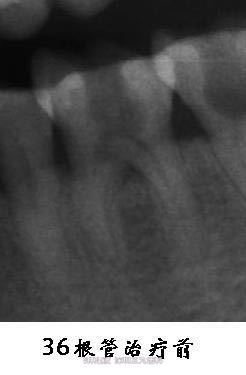

下颌磨牙侧枝根管一例

左下后牙外院拔髓后转我门诊治疗。

36髓腔和根管空虚。

处理:36根管治疗